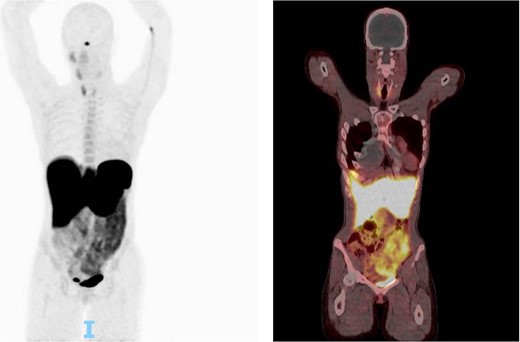

A transverse neck incision was used at the surgical approach of choice. At the posterior aspect of the left carotid bifurcation, the tumor was densely adherent to the arterial wall, and a portion of the carotid wall was taken with the tumor (Fig. 2). The patient tolerated the procedure well and had an uneventful postoperative course. She began a 2-week course of clopidogrel and a 3-month course of aspirin to prevent complications associated with the ICA repair. Pathology revealed a paraganglioma that demonstrated loss of succinate dehydrogenase B (SDHB) expression and stained positive for synaptophysin and S100. The patient was referred for genetic testing, which identified a pathogenic SDHB variant associated with hereditary paraganglioma-pheochromocytoma syndrome. She additionally underwent a PET scan, which revealed a left level II-B lesion (Fig. 3), consistent with metastatic neuroendocrine disease.

One hour after 5.4 millicurie of fludeoxyglucose injected this shows a CT scan followed up by PET scan. No suspicious focal activity was noted. Physiologic activity was noted in the right parotid/salivary glands minimally on the left mandibular gland, and bilateral thyroid, more on the right thyroid. Otherwise, no abnormal uptake was noted in the left neck. Presumed postop changes were seen in the left neck.